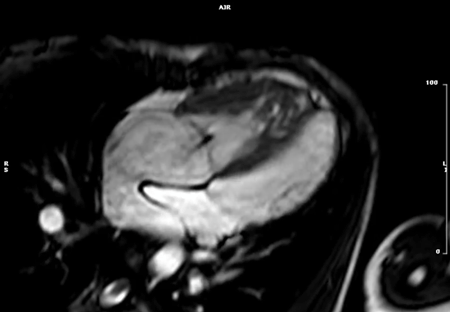

4. bSSFP長軸像シネMRI(Fig. 5

• 左室短軸断面以外に以下の基本3断面の撮影をする.検査時間の関係で,心臓全体をカバーするような撮影は行わず,撮影範囲は該当する3断面のみとすることが一般的である.

1. 四腔長軸像:二腔長軸像上で,僧房弁の中心,三尖弁の中心および心尖を通る断面.

2. 左室二腔像:すでに得られた垂直長軸断面から左室前壁・下壁を通るように設定.

3. 左室三腔像:心尖と僧房弁の中央を通り,左室流出路(LVOT)の中心と大動脈弁を含む断面.

Pediatric Cardiology and Cardiac Surgery 40(4): 260-271 (2024)

Fig. 5 Left: 4-chamber long axis cine image. Center: 2-chamber long axis cine image. Right: 3-chamber long axis cine image.